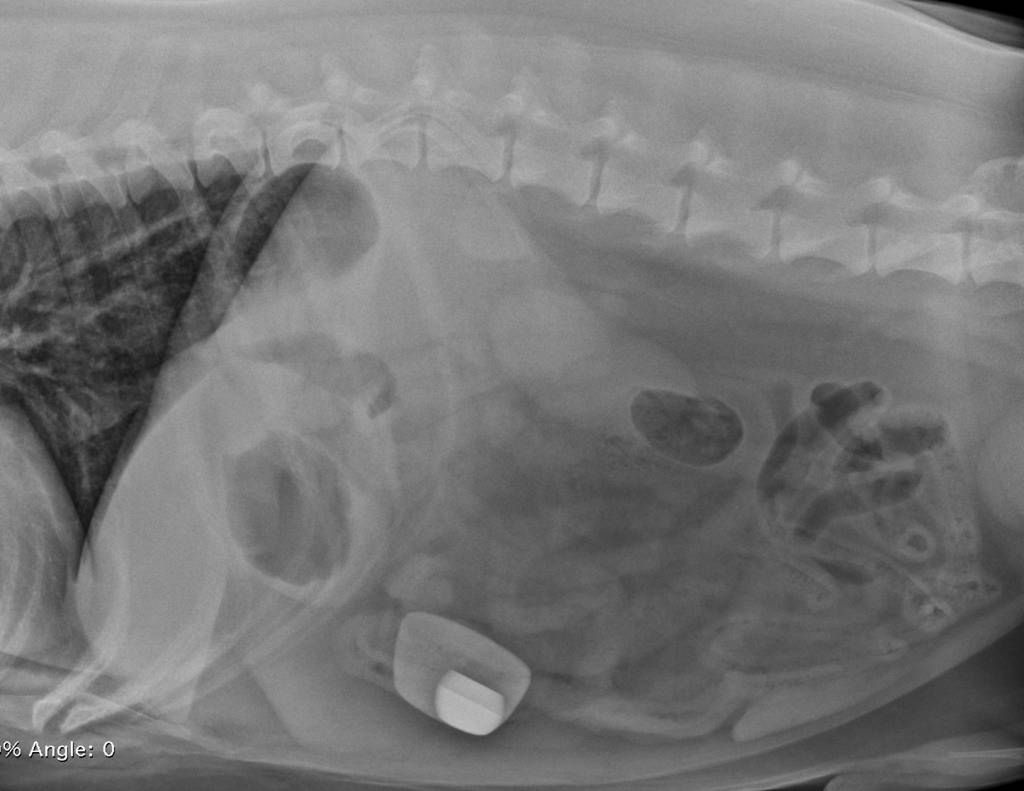

/ 11Co zjadła?

Obraz

© Veterinary Practice News/Lauren Flanagan, DVM, of Pepperell Veterinary Hospital in Pepperell, Mass.

Zwyciężyła półroczna angielska buldożka Leia. Właściciel dał jej do obgryzania 12-cm kość. Nie przewidział, że suczka połknie ją w całości.